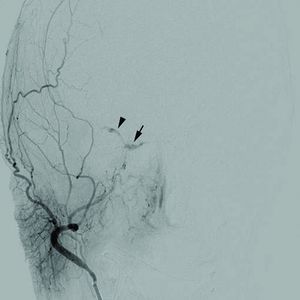

1471-2415-12-28-1Cerebral angiogram.jpg

Cerebral angiogram of a carotid-cavernous fistula

كما تُدرس الأوعية الدموية التي تغذي الدماغ بوساطة الأمواج فوق الصوتية أو بطرق أخرى (كتصوير الشرايين بالقثطرة أو بالمرنان المغنطيسي). والهدف من ذلك كله تحديد ما إذا كان هناك شريان متضيق وبحاجة إلى التوسيع.

أما التشخيص فقد يعتمد على عدة إجراءات منها تصوير الدماغ (الطبقي المحوري وأحياناً المرنان المغنطيسي) أو إجراء بزل قطني لتحري وجود الدم في السائل الدماغي الشوكي. ومن الإجراءات المهمة تصوير الشرايين الدماغية (بوساطة القثطرة) للتحري عن وجود تشوهات وعائية.